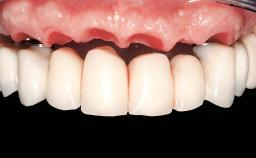

Immediate Loading of Eight Implants in the Maxilla and Six Implants in the Mandible and Final Restoration with Three-Unit and Four-Unit FDPs

Extensive scientific evidence has confirmed that immediately loaded implants with fixed full-arch provisional restorations can osseointegrate with success rates similar to conventionally or delayed loaded implants. A number of immediate-provisionalization techniques for edentulous jaws have been described. Some protocols differ when it comes to prefabricated provisional templates versus complete denture conversion; intrasurgical impressions versus direct relining; and cemented versus screw-retained provisional restorations. In this context, complete-denture conversion has been proposed for either intrasurgical impressions or direct relining. Another possibility is the utilization of a prefabricated provisional to be adapted either in the mouth (by direct relining) or in the laboratory (on a working model obtained from an intrasurgical impression).

Prosthesis Type FDP

SAC Level Complex

Defining Characteristics Fully edentulous upper jaw to be rehabilitated with an implant-borne fixed dental prosthesis

Loading Protocol Immediate

Esthetic Risk High